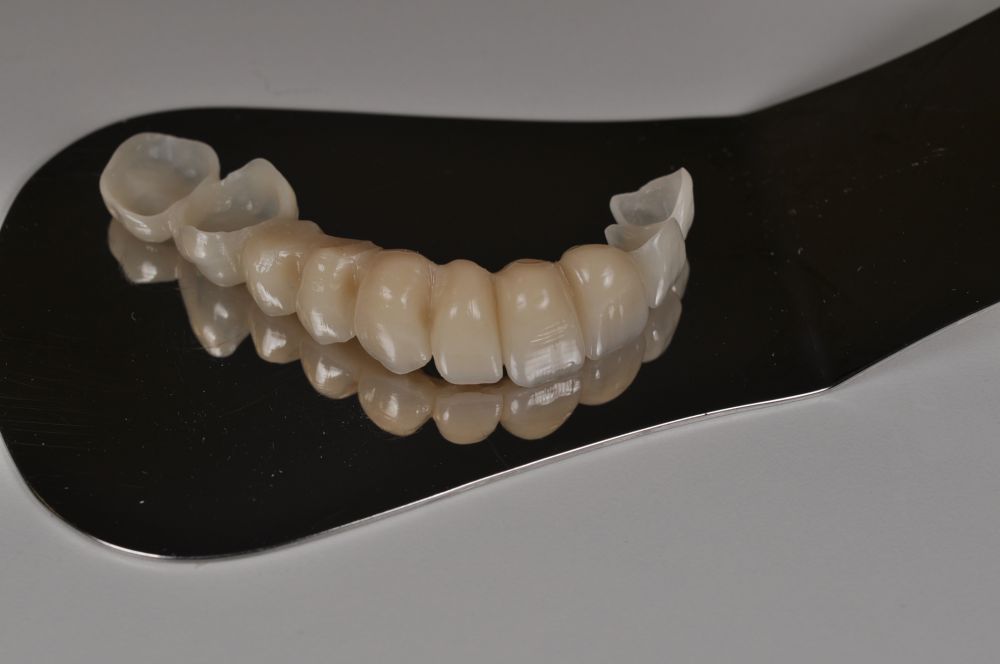

Para la fabricación de las estructuras, se eligió el óxido de zirconio monolítico como material restaurador sobre interfases metálicas en el puente implantosoportado, y coronas de óxido de zirconio monolítico en los dientes tallados previamente (1.7, 1.6, 2.2 y 2.3). Se tomaron impresiones de cubeta abierta con silicona de adición pesada y fluida (Zhermack Elite HD, Gmbh). Se realizó una prueba de pasividad analógica y el resto del proceso se confeccionó de manera digital, por lo que se hicieron pruebas estéticas de dientes impresas en 3D sobre interfases metálicas, para hacer todos los ajustes de función y estética previos al fresado del zirconio monolítico (Figuras 11, 12 y 13).

El día de la colocación de las estructuras, se arenó el interior de las coronas dentosoportadas con óxido de aluminio de 50 m y fueron cementadas con cemento de resina Multilink Ò. El puente implantosoportado se atornilló al torque indicado (20Nw) (Figuras 14, 15, 16 y 17).